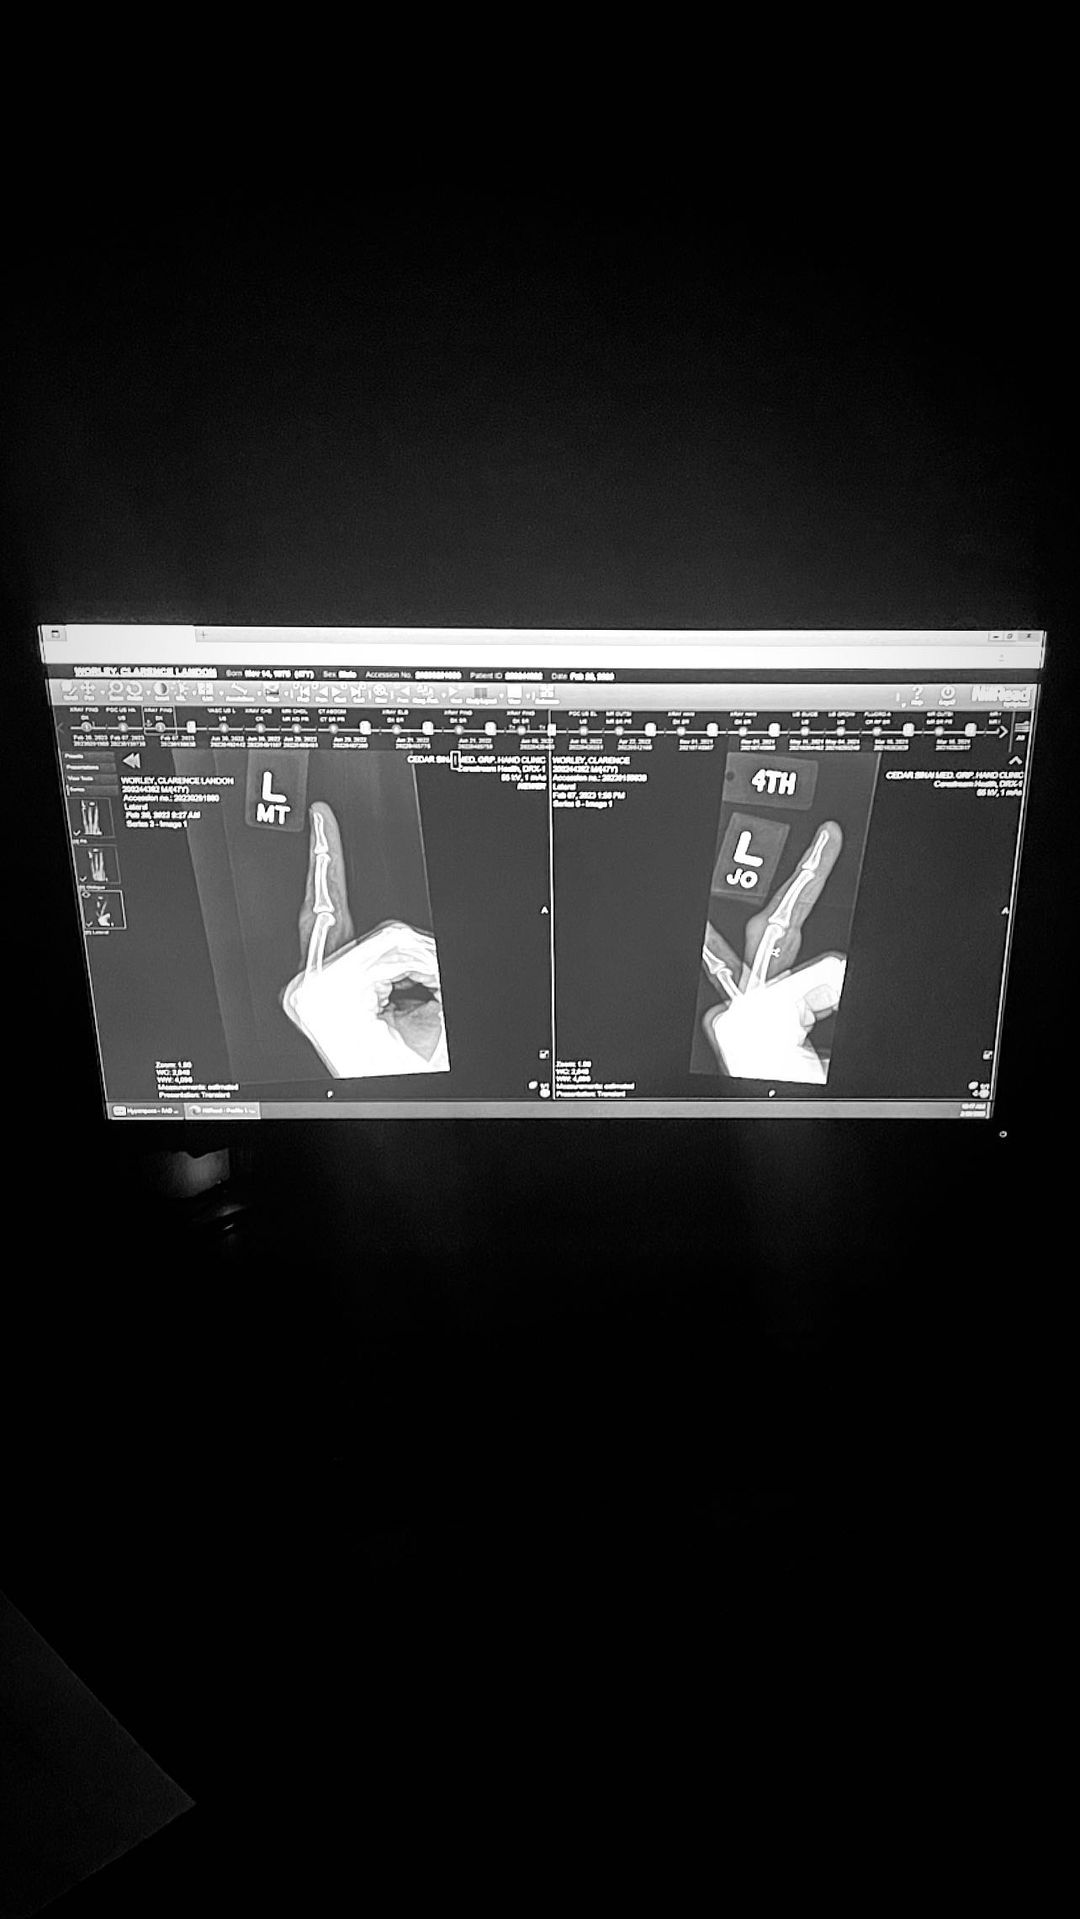

Музыкант разместил в Instagram Stories фотографию рентгеновского снимка, на котором видно травму безымянного пальца на левой руке. Похоже, у Трэвиса сильный вывих, так что пока ему придется повременить с репетициями и полностью восстановиться. Баркер не стал делиться подробностями инцидента.

Фото: Instagram @fog.again/ @travisbarker